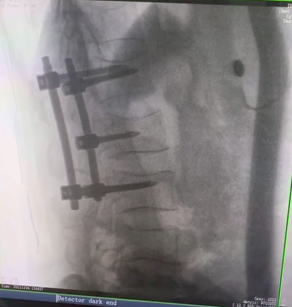

例如治疗先天性脊柱侧后凸畸形,由于脊柱自身复杂的解剖结构限制,使得脊柱外科手术对于精确度有着较高要求。以往我们只能采用传统的正侧位图像来判断螺钉置入的位置,现在三维C形臂特有的类CT断层成像,使得治疗过程可视化,立体化,在术中非常直观地判断螺钉植入的准确度。可有效引导术者植入后路螺钉并切除半锥体。同时可以在术中实时验证手术效果。有效地缩短了手术时间,降低手术风险,避免了不必要的术后翻修手术。

另外,三维C形臂采用12英寸(30cm x 30cm)的平板探测器,成像区域大,有效成像面积比9英寸传统影增提升了100%,可一次拍七节颈椎、五节腰椎、十二节胸椎、双侧骶髂关节、股骨头及单侧盆骨。